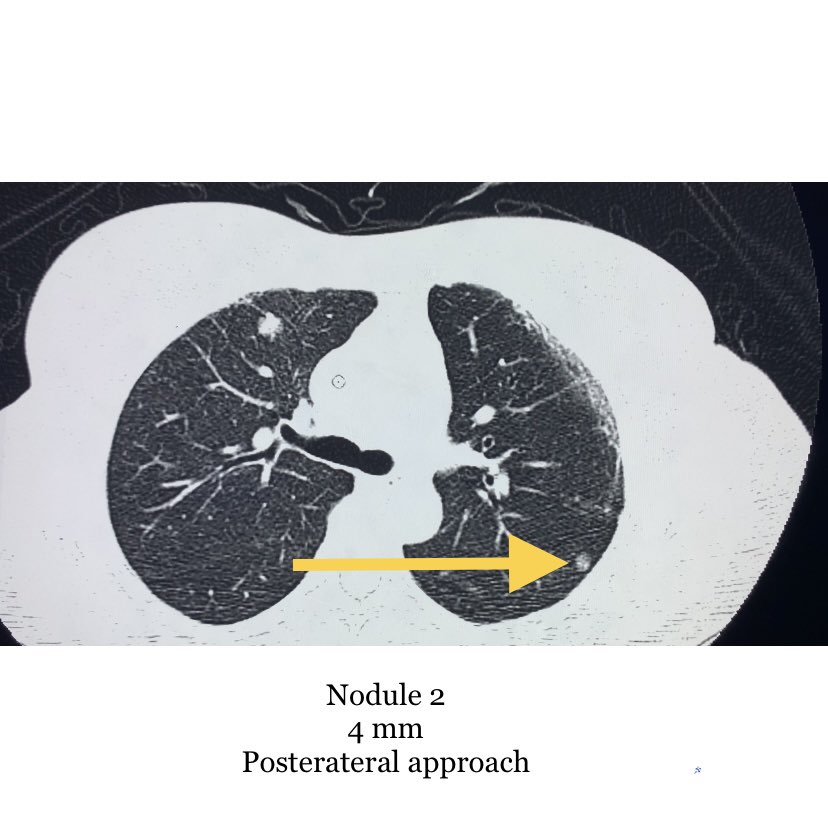

@evascularrounds @bhavinj @SRajesh_IR @No_cut_surgery @keithppereira @lenonjdee @_backtable @Dr_AkshayBaheti @SandeepBaglaMD @iRadRock @TomG_IR @Watts_IR @IrShaileshgupta @vascularIR Agreed, I would go for #4. Large enough to get adequate tissue, peripheral enough to limit risks. While I often like anterior approaches to enable supine positioning, the breast tissue, IMA, and small nodule size make #1 a little more complicated.

Reference for CT guided lung lesion biopsy. Nodule preference for biopsy and why?

Nodule 1, 2, 3 or 4?

@bhavinj @SRajesh_IR @No_cut_surgery @keithppereira @lenonjdee @_backtable @Dr_AkshayBaheti @SandeepBaglaMD @iRadRock @TomG_IR @Watts_IR @IrShaileshgupta @Golden_IR @vascularIR